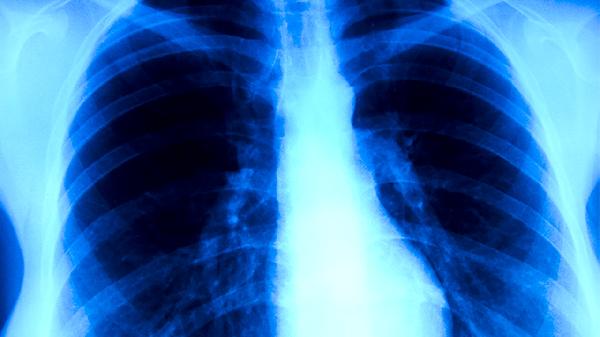

耐药性肺结核患者需严格遵医嘱完成全程治疗,不可自行停药或减量。每日开窗通风2-3次,佩戴口罩避免传染他人。定期复查胸部CT和痰培养,接触者应进行结核菌素试验筛查。保持乐观心态配合治疗,多数患者经规范管理可获临床治愈。